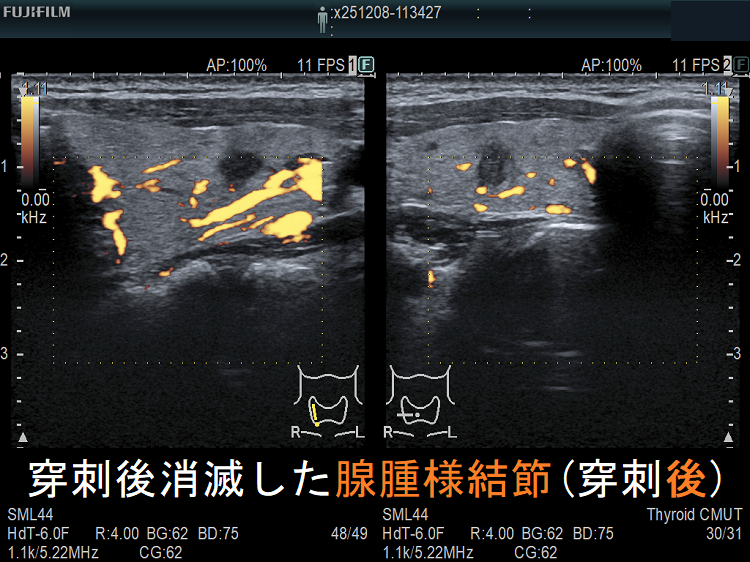

穿刺細胞診後内部融解

ケース①

ケース②

![穿刺後消滅した腺腫様結節(穿刺後)ドプラーモード[拡大] 穿刺後消滅した腺腫様結節(穿刺後)ドプラーモード[拡大]](../images/basic/basic5/images20251216212330.png)